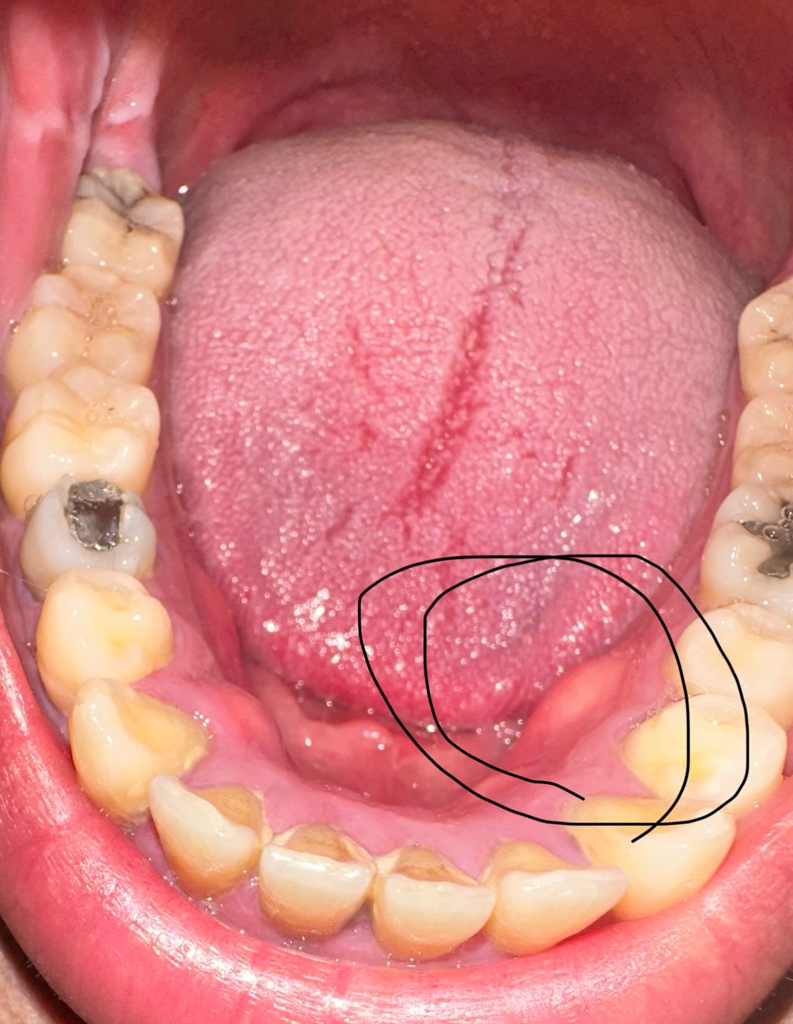

잇몸뼈가 튀어나온곳이 자극을 받아서 염증이 생긴거일수도 잇고 그 부위 치아 뿌리끝에서 나오는 염증일수 있으니 일단 치과에 가셔서 검진을 받아보시는게 좋을것같습니다.

치주농양입니다. 일단 짜서 사이즈가 줄었지만 다시 재발합니다. 치과에 가서 절개하고 항생제 복용해야 합니다.

치근단 질환이 있는 경우에 해당 부위에 붓고 고름이 나올 수 있습니다 치근 단 질환은 치주질환으로 인해서 생기기도 하고 치아 안쪽에 신경이 감염이 되면서 생길 수 있습니다 염증의 원인을 제거해야 치근단 질환이 줄어들기 때문에 치과에서 진료를 받고 치료를 받아 보는 것이 좋습니다